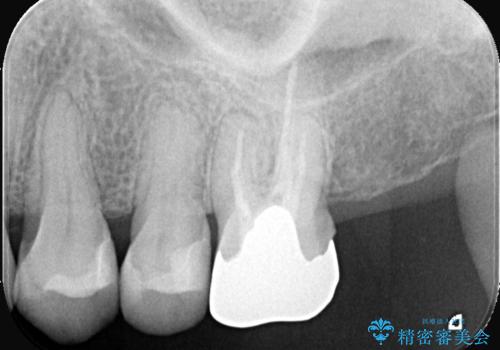

レントゲンおよび精密診査の結果、過去に根の治療を終えた根尖部に再び炎症(根尖病変)が認められました。被せ物の適合が悪くなっていたことから、隙間から細菌が侵入したことが原因と考えられます。歯を長持ちさせるため、まずは古い被せ物と土台を外して根の内部を徹底的に洗浄する再根管治療を行い、その後、適合性と審美性に優れたオールセラミッククラウンで修復する計画を立案しました。

治療は、根管内の感染源を顕微鏡下で徹底的に除去・消毒する精密再根管治療から行いました。